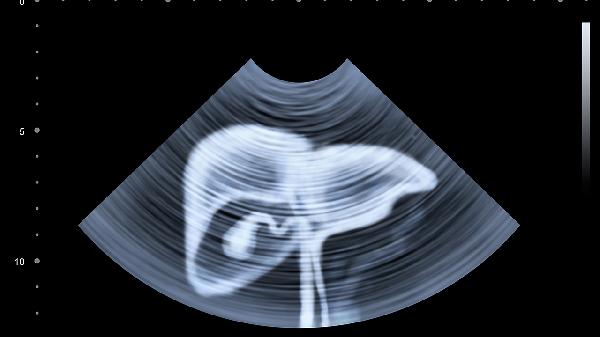

腹部脂肪过多会引起什么症状

腹部脂肪过多可能引发代谢综合征、心血管疾病和呼吸系统问题。原因包括不良饮食习惯、缺乏运动、遗传因素和激素失衡。改善方法包括调整饮食、增加运动、药物治疗和手术干预。